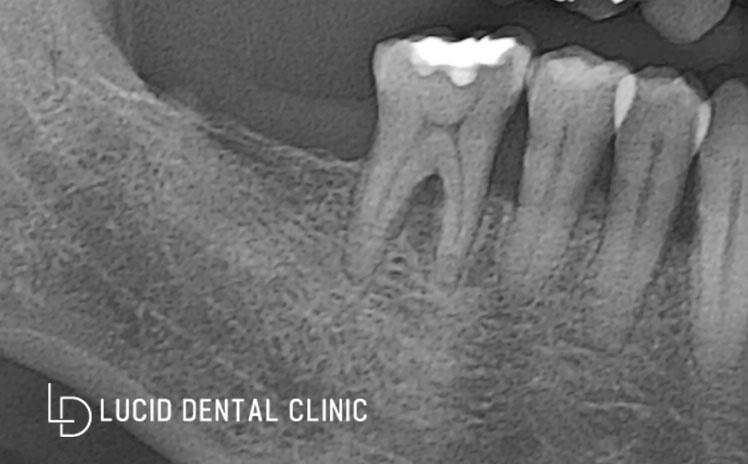

사진을 보게 되면

이전에 이미 임플란트를

많이 식립하고 나서 내원하셨는데요

나사 볼트처럼 보이는 걸

'픽스처'라 하는데, 이것이 잇몸뼈조직에

단단히 잘 유착이 되어야 됩니다.

이를 위해서는 초기 진단이 아주 중요하죠.

- 두 번째 위에서 좌측 (소구치)

환자께서 통증이 있다고

말씀하기도 했고 뿌리도 내려와

동요(흔들림)가 나타나고 있었는데요.

1️⃣ 흔들리는 치아는 치료해도

치주 조직이 뿌리를 고정하지 못하고

2️⃣ 치은과 치아 사이에 공간이 생겨 흔들리면서

음식물이 안쪽으로 들어가 청결 관리도 어렵고

3️⃣ 염증도 악화되어 골 소실로 이어지기 때문에

치료해도 의미가 없을 수 있습니다.

이때는 적절한 시기에 발치해야.

잇몸병이 나빠지는 걸 미리 예방할 수 있습니다.